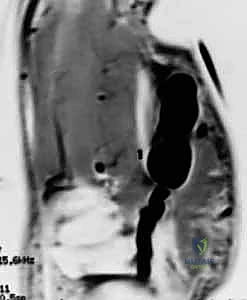

- التصوير بالموجات فوق الصوتية (Ultrasound): طريقة سريعة وفعالة لتأكيد التشخيص وتحديد ما إذا كان الورم يحيط بالأوعية الدموية.

- الرنين المغناطيسي (MRI): هو المعيار الذهبي الذي يطلبه الدكتور هطيف في الحالات المعقدة أو الأورام العميقة غير الظاهرة، لتخطيط الجراحة بدقة متناهية ومعرفة ارتباط الورم بالهياكل الحيوية.